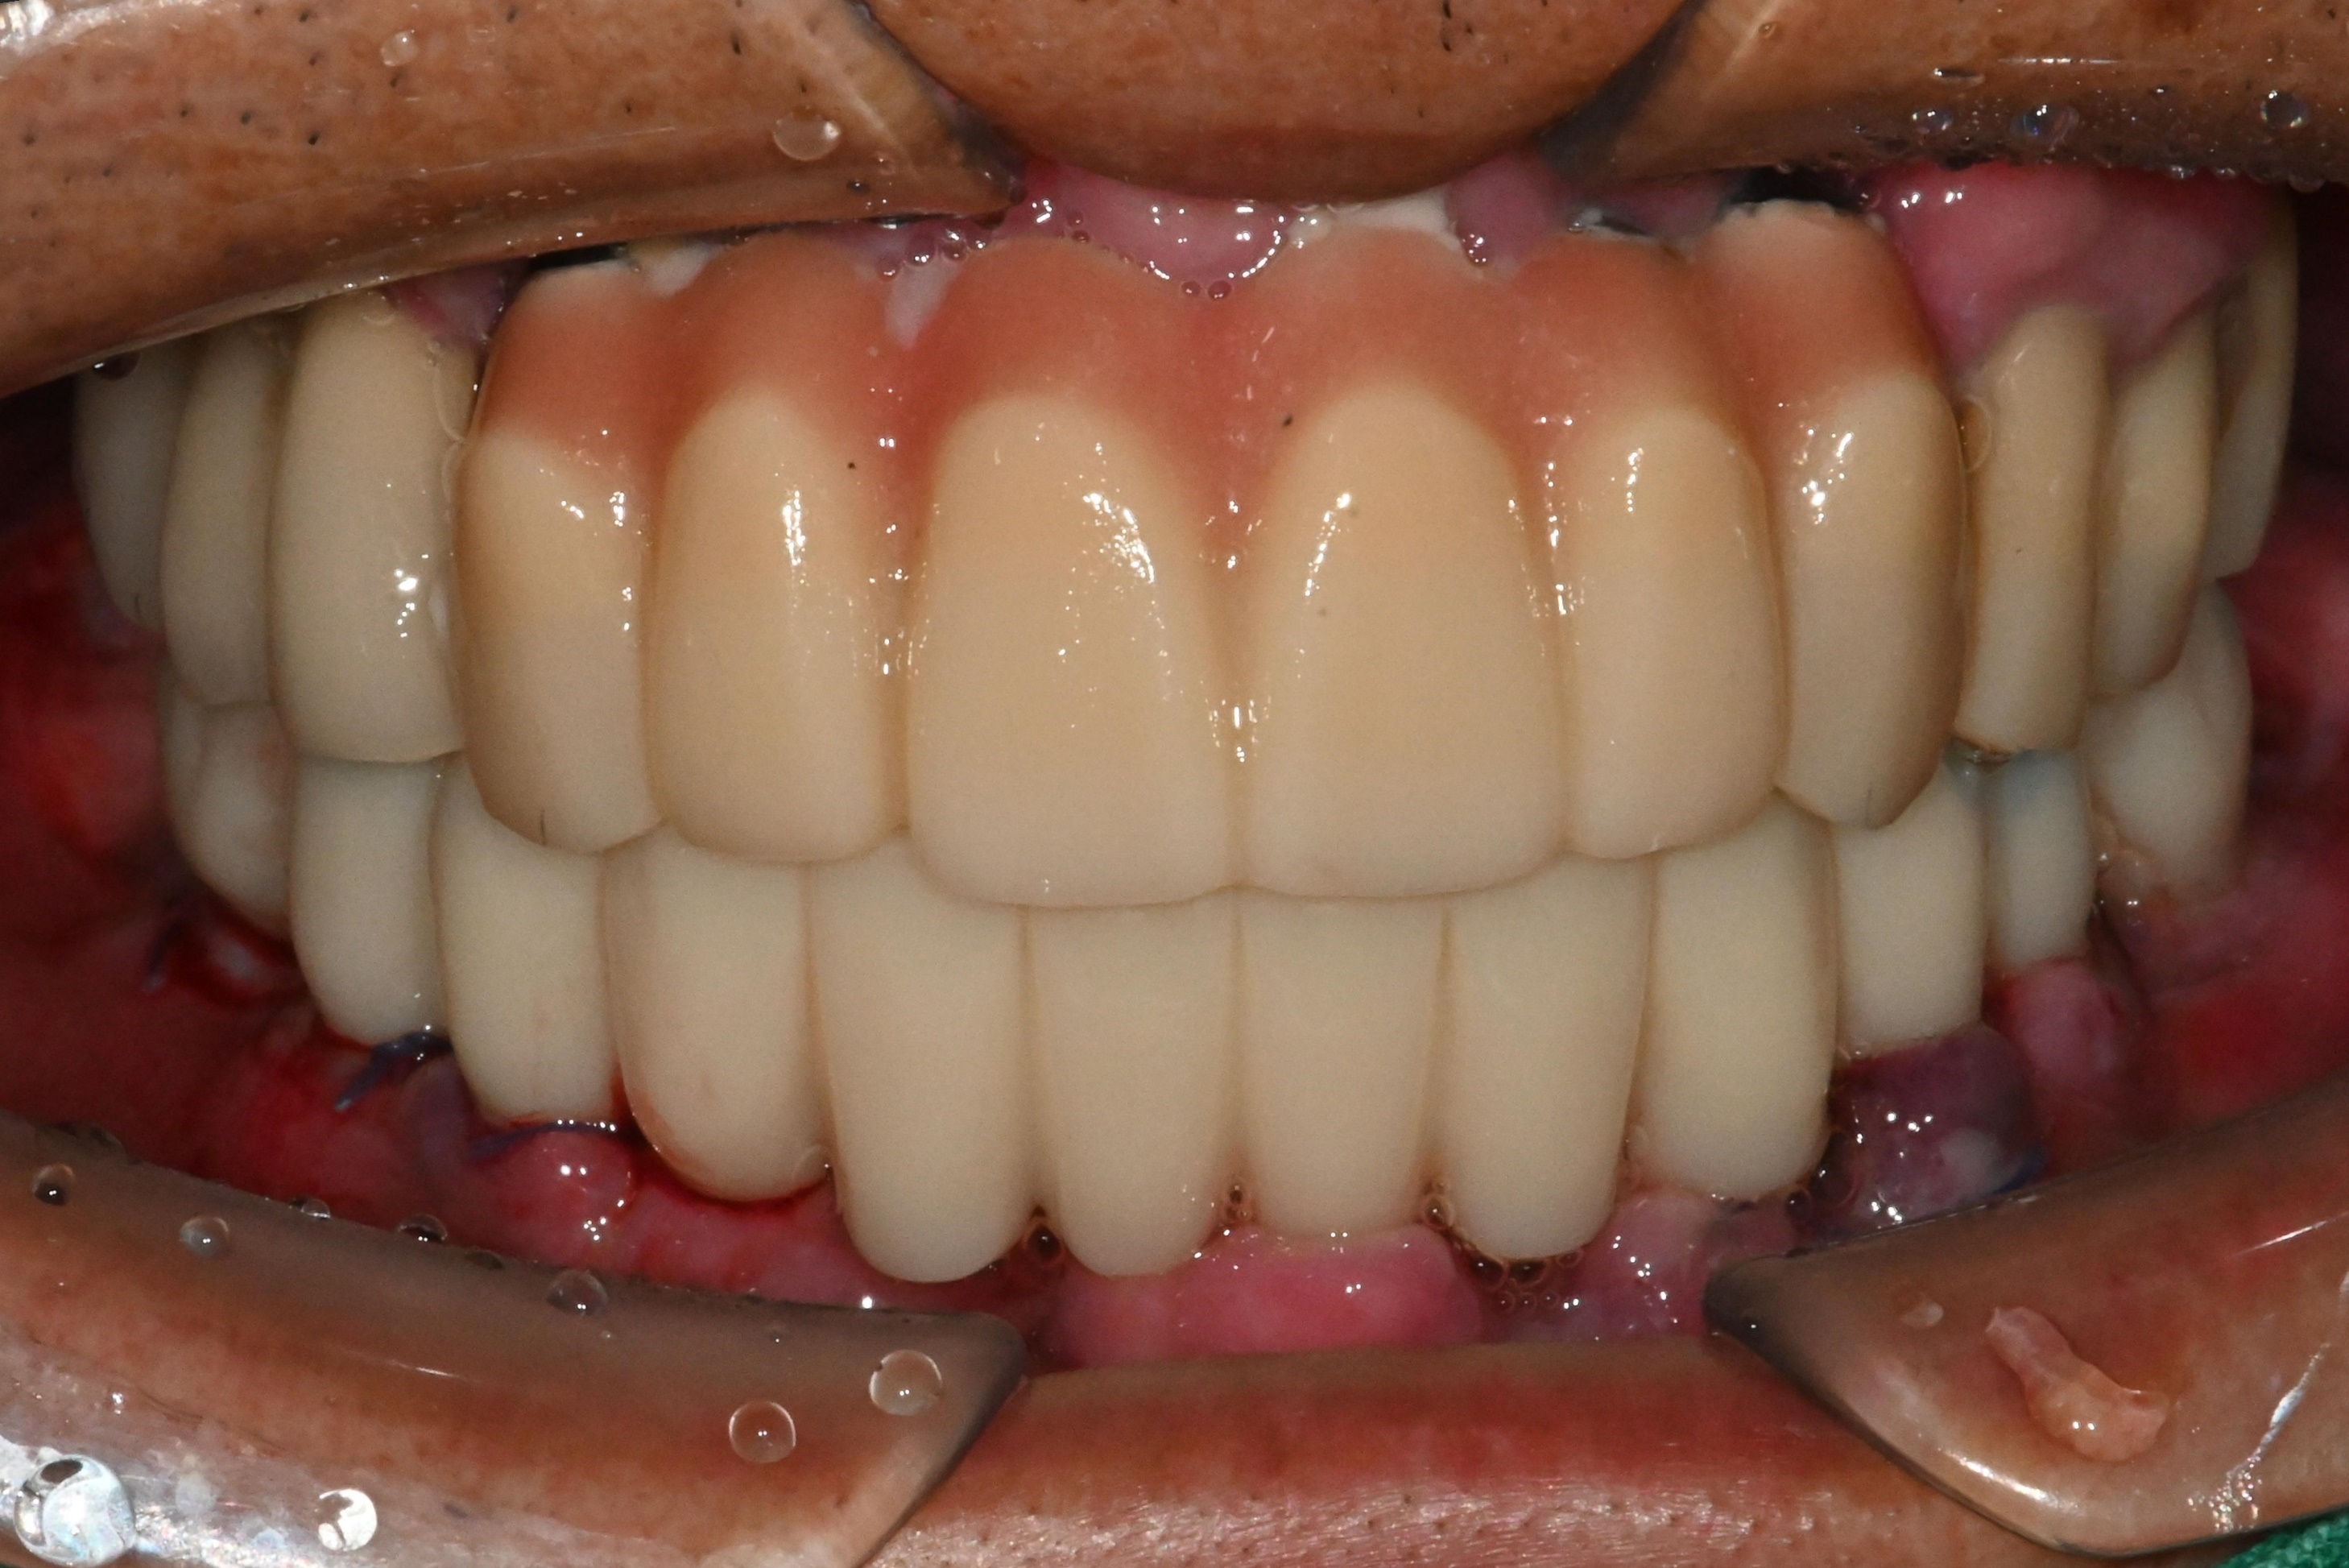

수술 전 후 사진을 비교해보면

더욱 명확히 들어납니다.

3개월 후에는

임시치아와 동일한 모양의

세멘트 없는

고퀄리티 스크류 타입 보철물

장착하고 마무리 하게 됩니다 ^^